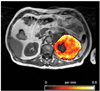

The success of cancer therapy can be difficult to predict, as its efficacy is often predicated upon characteristics of the cancer, treatment, and individual that are not fully understood or are difficult to ascertain. Monitoring the response of disease to treatment is therefore essential and has traditionally been characterized by changes in tumor volume. However, in many instances, this singular measure is insufficient for predicting treatment effects on patient survival. Molecular imaging allows repeated in vivo measurement of many critical molecular features of neoplasm, such as metabolism, proliferation, angiogenesis, hypoxia, and apoptosis, which can be employed for monitoring therapeutic response. In this review, we examine the current methods for evaluating response to treatment and provide an overview of emerging PET molecular imaging methods that will help guide future cancer therapies.